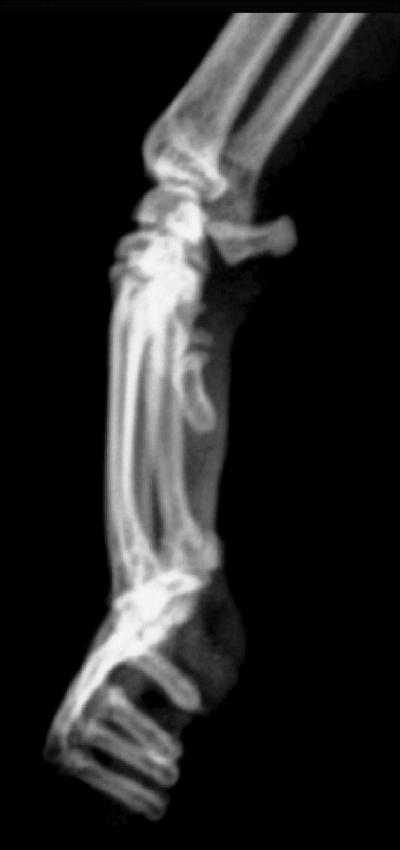

The surgical guideline for performing declawing, as recommended by Diplomates of the American College of Veterinary Surgeons, is to remove the entire third phalanx (P3), which is the most distal bone of the toe. Despite this, P3 fragments were found in 63% of the declawed cats in this study, reflecting poor or inappropriate surgical technique. While the occurrence of back pain and abnormal behaviors was increased in these cats, the authors emphasize that even optimal surgical technique does not eliminate the risks. They explain that removal of the distal phalanges forces the cat to bear weight on the soft cartilaginous ends of the middle phalanges (P2) that were previously shielded within joint spaces. Pain in these declawed phalanges prompts cats to choose a soft surface, such as carpet, in preference to the gravel-type substrate in the litter box; additionally, a painful declawed cat may react to being touched by resorting to biting as it has few or no claws left to defend itself with.

Radiograph credit: The surgery, which involves removing the distal bone of the toes, is banned in many countries. Nicole Martell-Moran.